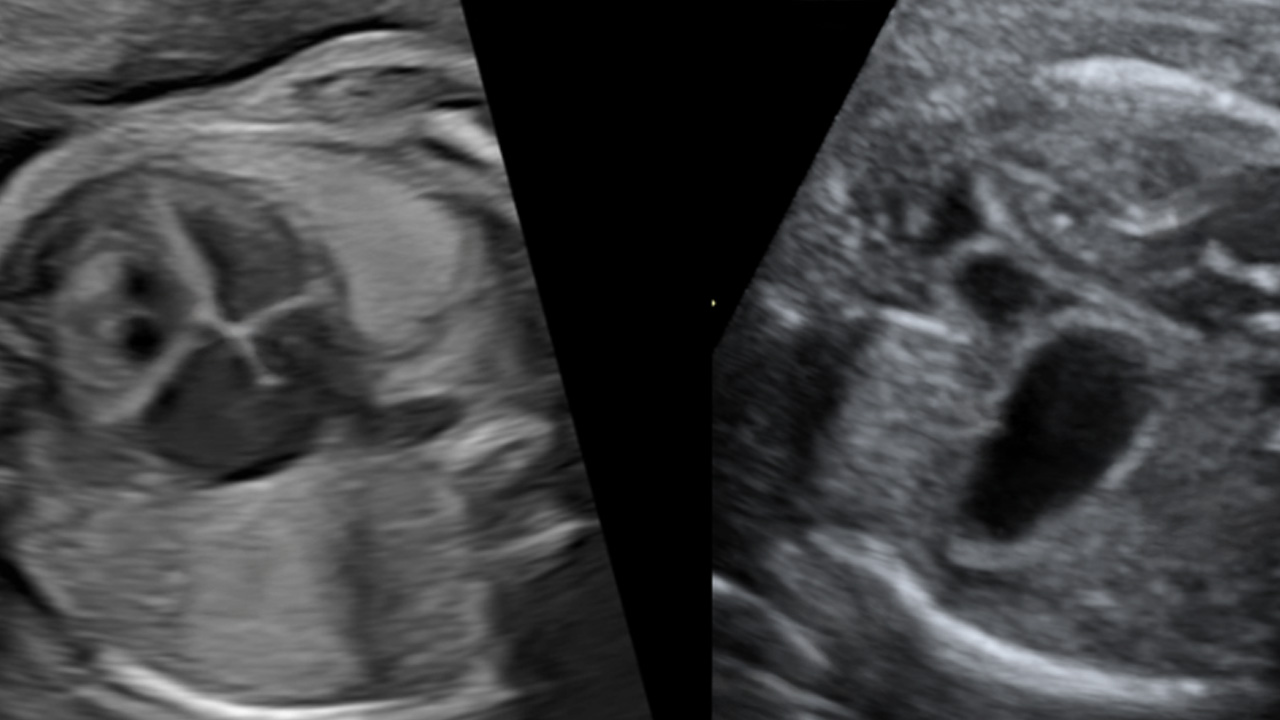

Our experts are pushing the limits of technology to advance fetal cardiology imaging by using an MRI-compatible Doppler ultrasound device and 4D flow with fetal cardiac MRI. This allows us to better analyze the function of the fetal heart, get more accurate diagnoses and create more targeted care plans.